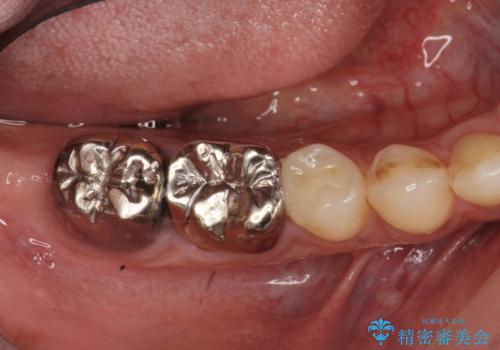

- 上顎臼歯部の欠損にブリッジ治療、目立つ下顎奥歯の銀歯をセラミックへの置き換えを希望され来院されました。

審美性と耐久性に優れるフルジルコニアクラウンでの治療を計画します。